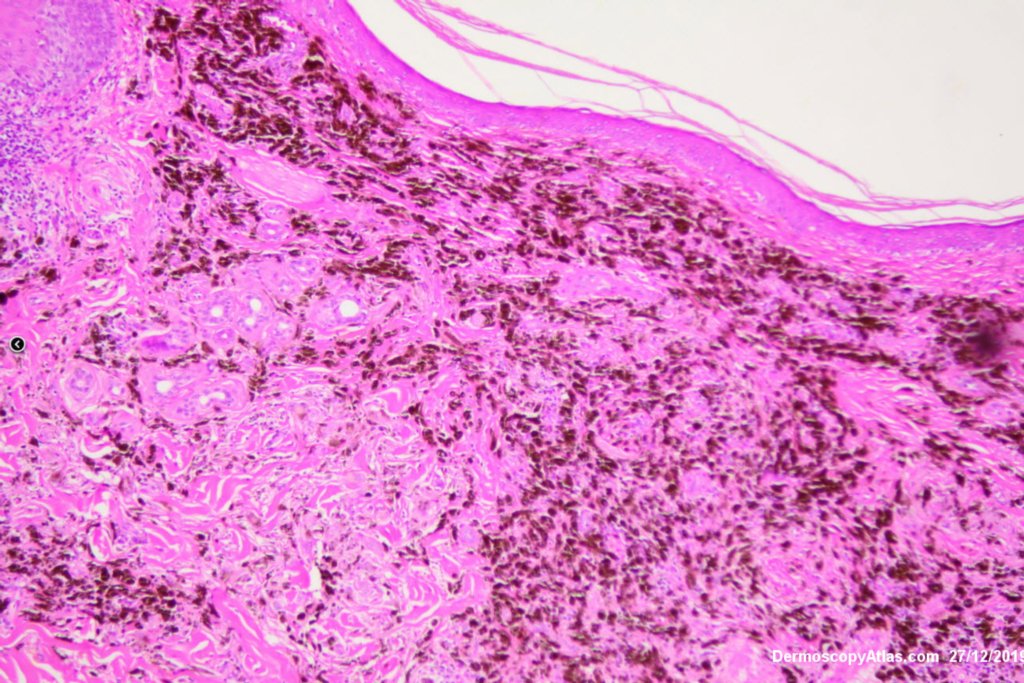

Image Number #3527 (Melanoma metastases)

Diagnosis: Melanoma metastases

Description: Background brown lesion with blue macules and papules developing

This elderly man had a preceeding lentigo maligna but subsequently developed in transit metastases as shown by the blue macules and papules on his cheek. He was treated with Keytruda. PET scan was negative for spread elsewhere.

It is important to treat lentigo maligna early to stop a situation like this from developing.